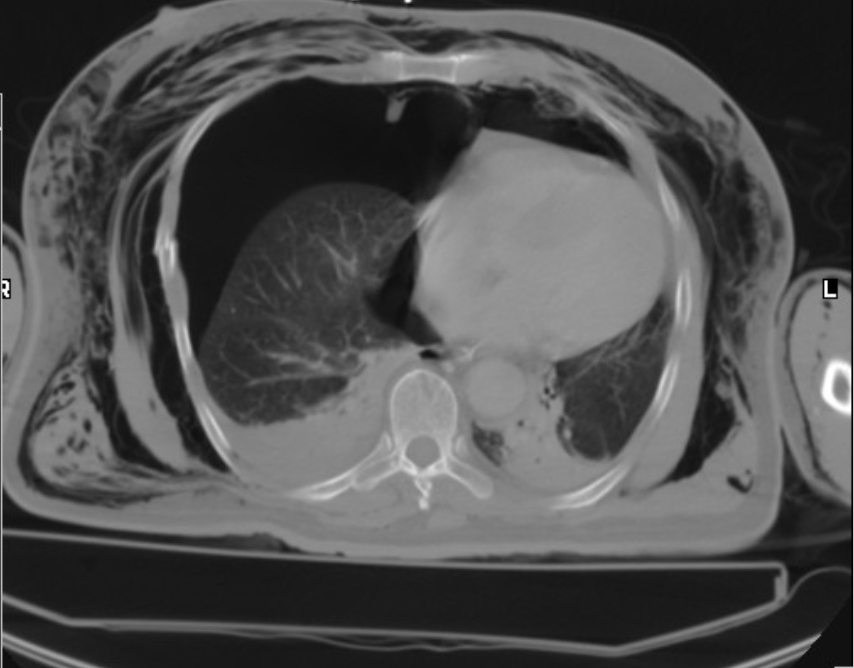

RA: pulmonary emboli

CT (most common and more accurate) shows filling defect, NUCMED ventilation study shows perfusion defect

serial CXR rarely to never done but show enlargement of affected vessels

[larger white area = pulmonary trunk leading to the right and left pulmonary arteries]